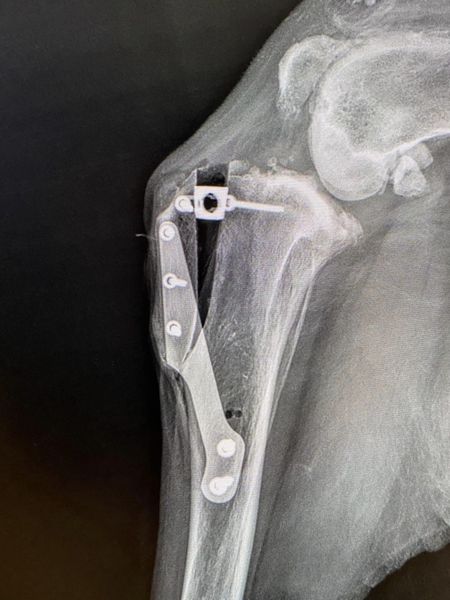

To były dwa dni pełne pasji, nauki i wymiany doświadczeń, podczas których zgłębialiśmy tajniki zabiegu TTA (Tibial Tuberosity Advancement), czyli operacyjnego przesunięcia guzowatości piszczelowej.

Uczestnicy mieli możliwość wypróbować nasze implanty w praktycznych demonstracjach, co pozwoliło zrozumieć procedurę TTA.